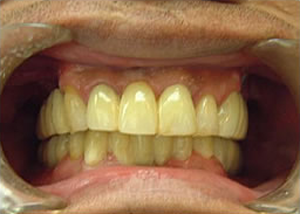

19.下は作った最終本物の歯が入りました。

これで治療終了。

開口器を入れた口元

治療完了

平成21年1月29日

(治療期間:1年7ヶ月)